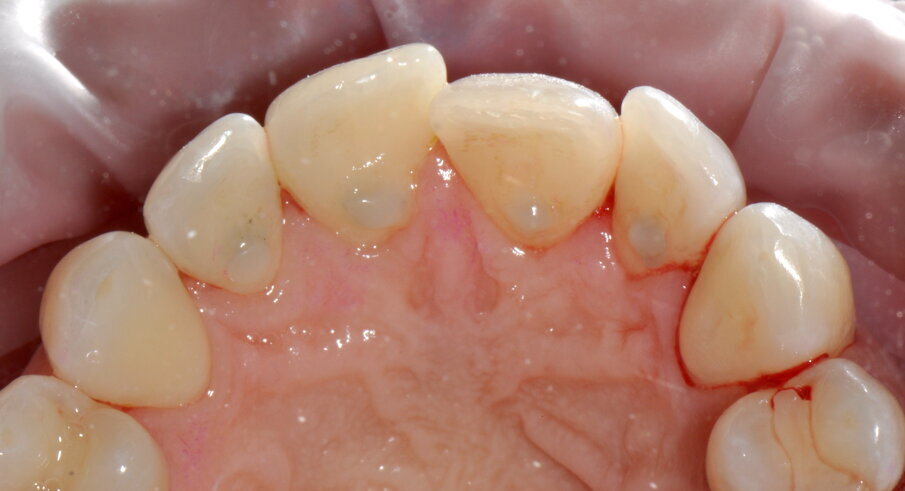

Figg. 1a-1c - Applicazione del rilevatore di placca che verrà usato come guida durante la terapia, nel versante vestibolare (1a), palatale (1b) e linguale (1c). Si noti lo scarso livello di igiene orale domiciliare e l’assenza di utilizzo dei presidi interdentali.

Figg. 2a-2c - Foto scattate dopo l’utilizzo del manipolo sopra-gengivale, nelle aree vestibolare (2a), palatale (2b) e linguale (2c), senza la detartrasi con strumento piezoelettrico.

Figg. 3a-3c - Termine della terapia. nelle visioni vestibolare (3a), palatale (3b) e linguale (3c).

Figg. 4a-4f - Confronto fra inizio e termine della terapia. Le immagini (4a-c) mostrano le aree vestibolare palatale e linguale prima della terapia, mentre le immagini (4d-f) mostrano le aree vestibolare palatale e linguale dopo della terapia.